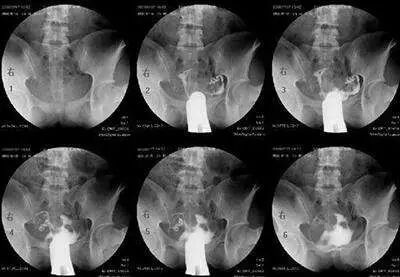

最常用的是输卵管造影(HSG)

医生会根据不孕的时间、可能的原因,来选择是否需要做HSG。

造影的时间一般在月经干净后3天到排卵之前,造影前不要有性生活,白带检查正常等等。造影后1周禁性生活,当月最好不要尝试怀孕。

不过现在的造影剂比较先进,一般代谢很快,假如不小心当月怀上,多数也没有问题。保险一点,等下次月经来过再试孕。